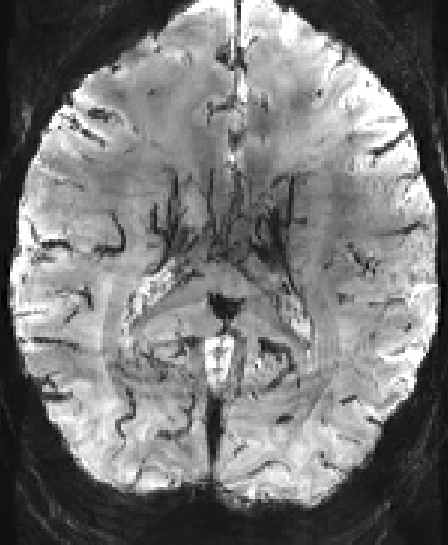

In this example, the range of the minimum intensity projection is changed.

LN_INTPRO -image BOLD.Mean.nii -min -direction 3 -range 5

LN_INTPRO -image BOLD.Mean.nii -min -direction 3 -range 15